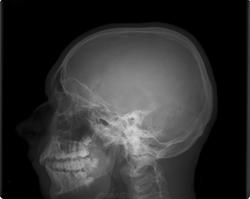

Молодой человек упал с турникета, 2 часа назад.При пальпации черепа ощущение хруста. Перелом? внутренней пластинки теменной кости.

Я, конечно, не специалист по переломам, но что-то подсказывает, что будет КТ. Сомневаюсь, что можно внутреннюю пластинку ощутить при пальпации, но не нравится чёткость добавочных "сосудистых" линий в ламбде...

Признаков перелома не вижу.

перелома визуально не определяется

То же признаков перелома не вижу